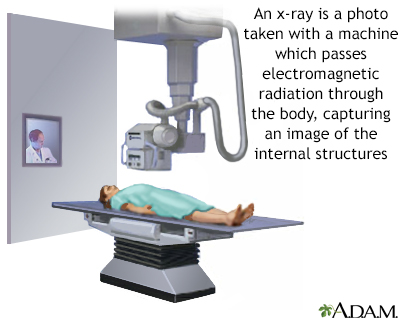

- Chest x-ray

- X-ray of bone and surrounding tissue

Some benign bone tumors go away on their own and do not need treatment. Your provider will closely monitor you. You will likely need regular imaging tests, such as x-rays, to see if the tumor shrinks or grows.